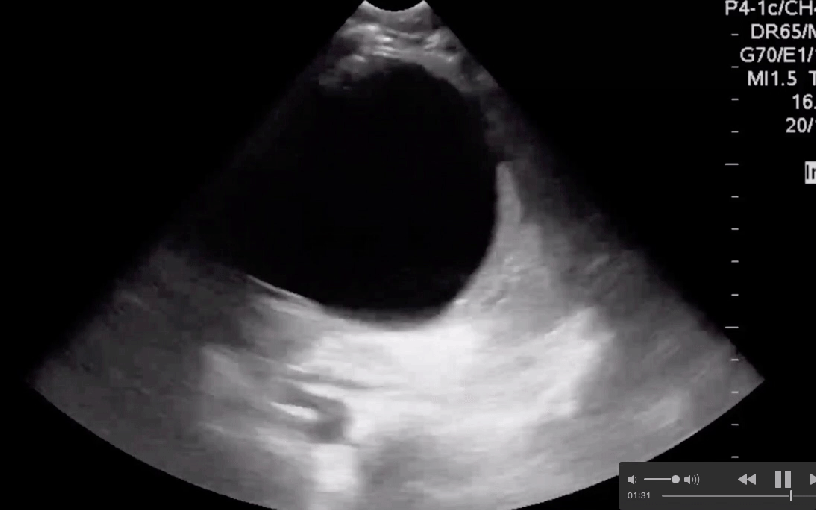

#Sono of the Week Splenic Cysts! They are rare, but can cause pain, infection and death. What causes them and what’s the management? #POCUS #Foamus #Foamed